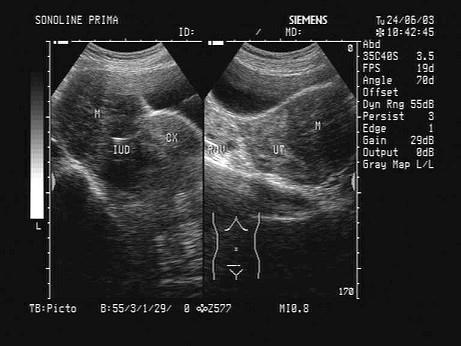

问题 女,33岁,因月经不调就诊,超声声像图如下,最可能的诊断为?(?)

选项 A.附件炎 B.子宫肌瘤 C.子宫腺肌症 D.子宫内膜癌 E.卵巢肿瘤

答案 B